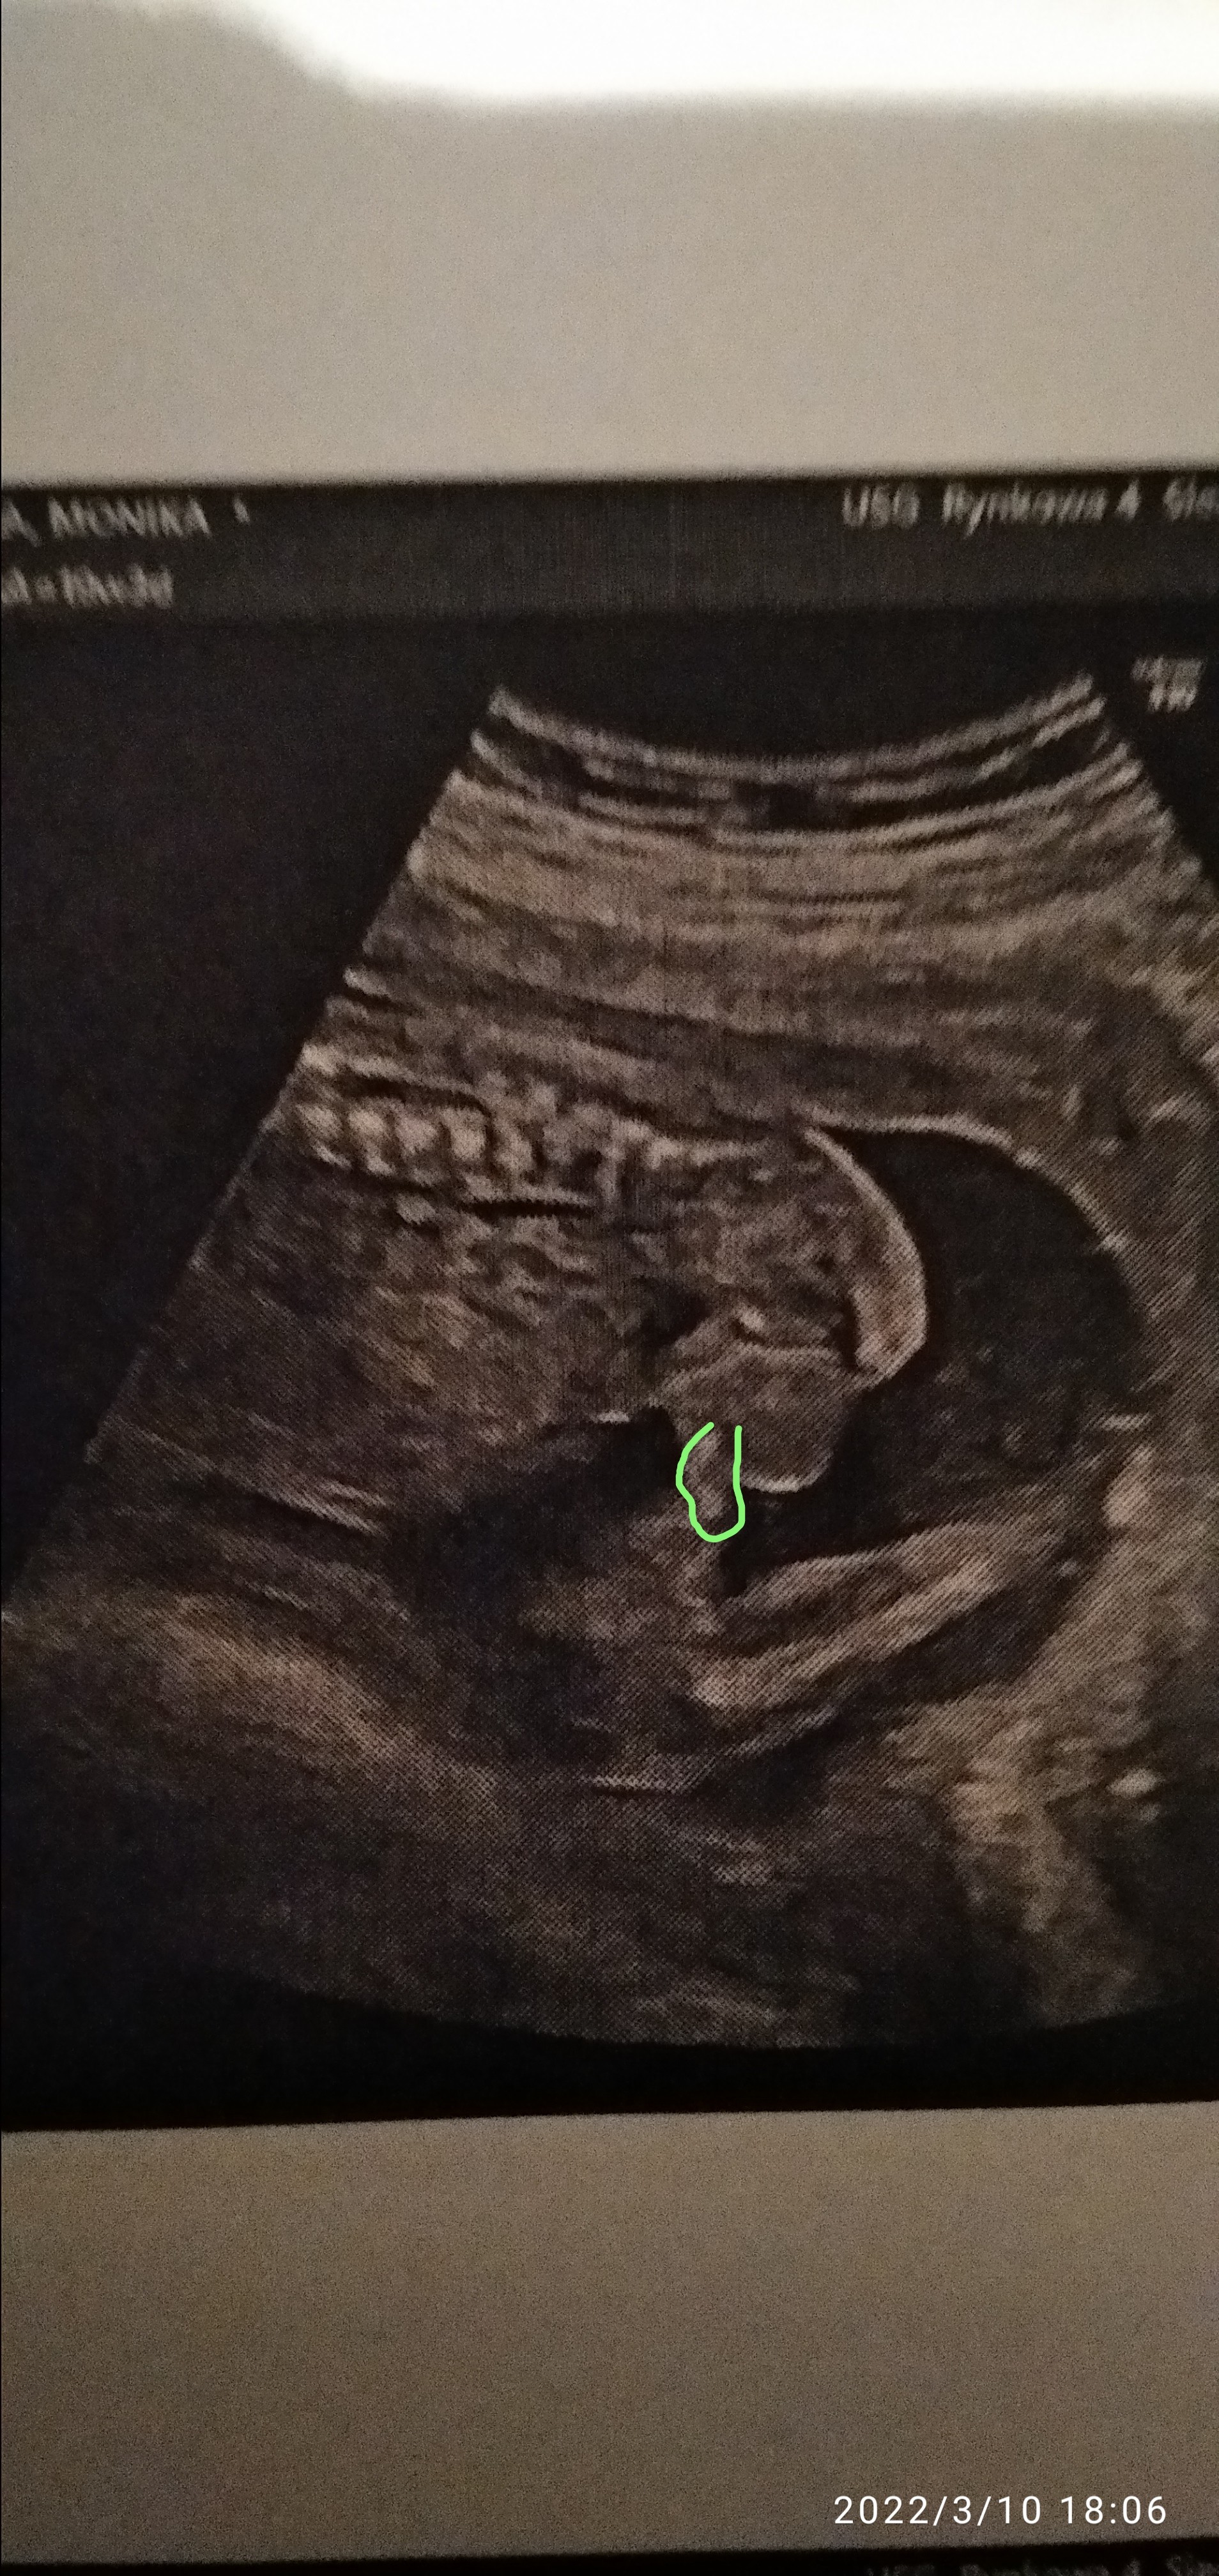

Cześć kobietki, skorzystam z tego wątku, bo na innym nikt nie odpisuje. Mam USG z 19 tygodnia ciąży, moim zdaniem jest to chłopiec, ale wprost lekarz nic nie powiedział. Jedynie skomentował, że widać w którym kierunku idzie płeć dziecka. Ja nie chcąc zrobić z siebie głupiej, nie dopytywałam. Zdjęcie jest z całkiem innej perspektywy, niż te wszystkie, które mamusie tutaj wstawiają.

Szkoda że to zdj z boku a nie od dołu. Na tym zdj może być to jądro tak mi się zdaje

Mamy, a myślicie, że to może być zwisający siusiak? Czy ja po prostu widzę to co chcę widzieć 😂

Ciężko powiedzieć w 100% ale wyglada jakby faktycznie były tam jąderka 😁